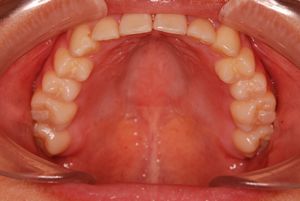

健康な小臼歯を抜いていません

矯正前                 矯正後

治療前 の 上アゴ です 動く矢印治療後 の 上アゴ です